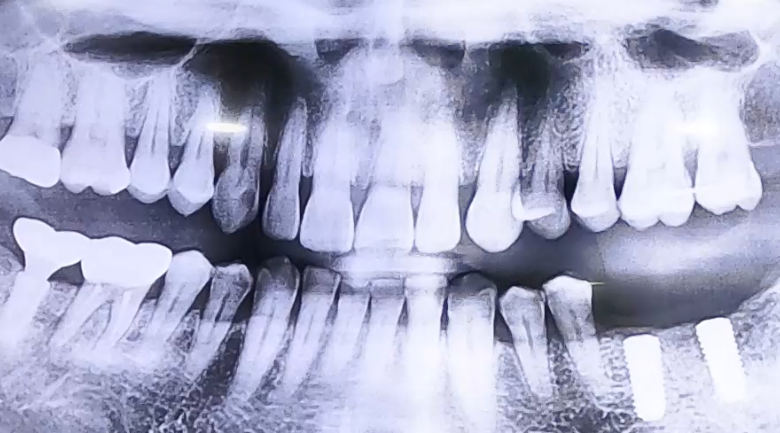

임플란트 보철이 깨진 사례

BEFORE

오래 전 진행하셨던 임플란트의 머리 부분 보철이

최근 깨지면서 내원해 주셨던 환자분이십니다.

왼쪽 아래 어금니를 발치하신 후 오랫동안 그대로 둔 상태로

오른쪽으로만 식사를 하시면서, 오른쪽 아래 큰 어금니 임플란트가 깨진 것이었는데요.

잇몸뼈 상태는 양호하였고 임플란트도 머리 부분만 파절되었기 때문에

임플란트 보철을 분리하고 머리 부분만 새로 제작해 드렸습니다.